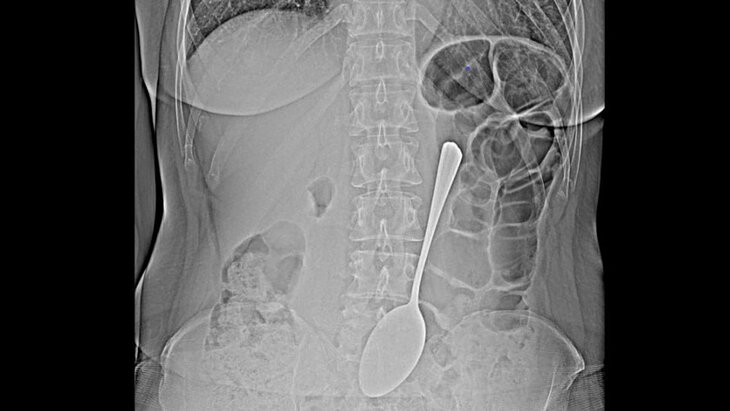

Фото: Республиканская клиническая больница скорой медицинской помощи имени Ангапова

По итогам обследования медики обнаружили столовую ложку в желудке женщины. При этом она не объяснила, каким образом прибор оказался в пищеварительном органе.

В ходе операции хирурги успешно извлекли инородное тело при помощи эндоскопа и специальных инструментов. Благодаря слаженной работе врачей столовый прибор не успел вызвать перфорацию желудка и кишечную непроходимость.